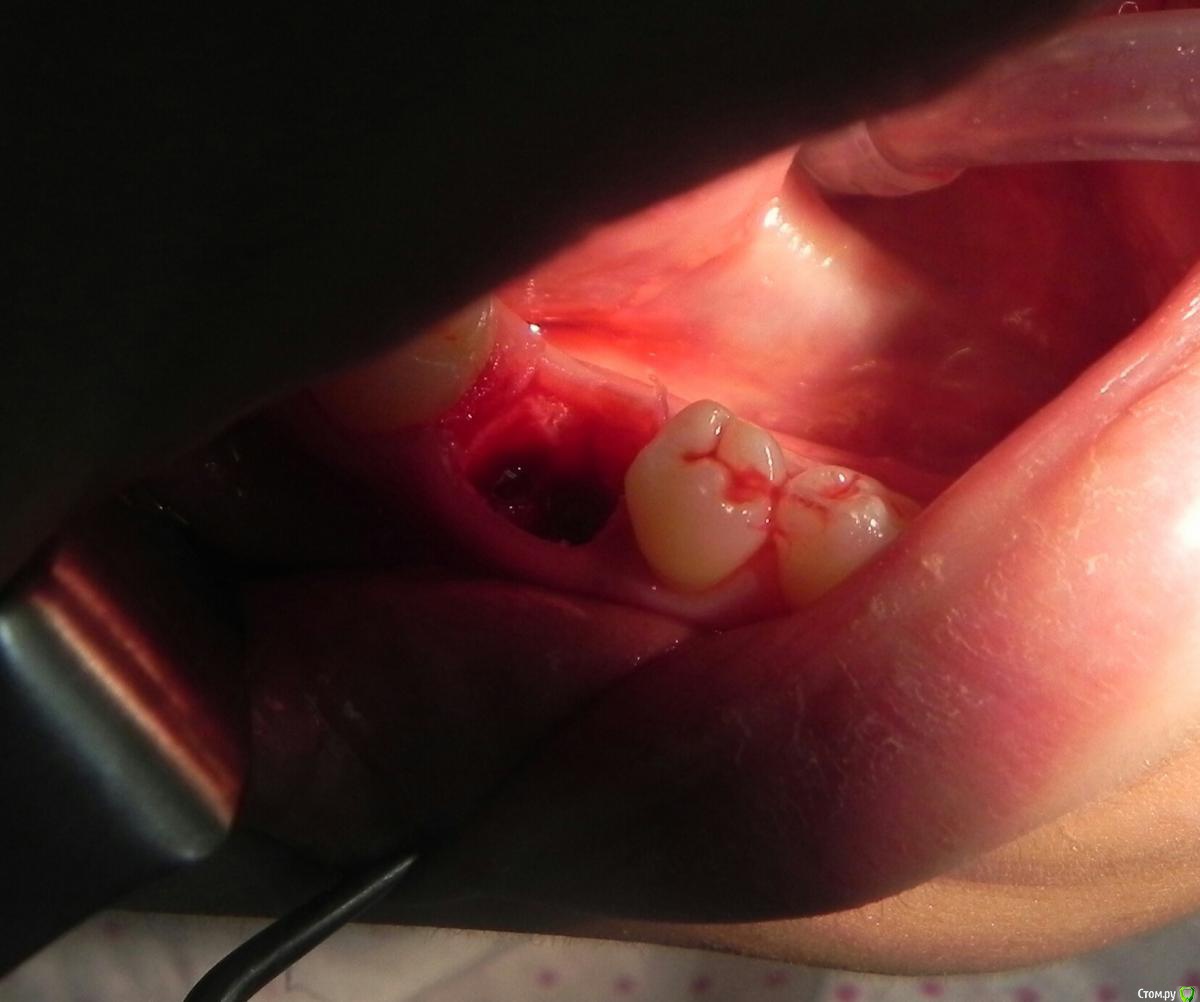

Kostoprav Опубликовано 24 мая, 2016 Поделиться Опубликовано 24 мая, 2016 удалил, вкрутил,графт gen oss, фдм.P.S. сори за плагиат) 3 Ссылка на комментарий